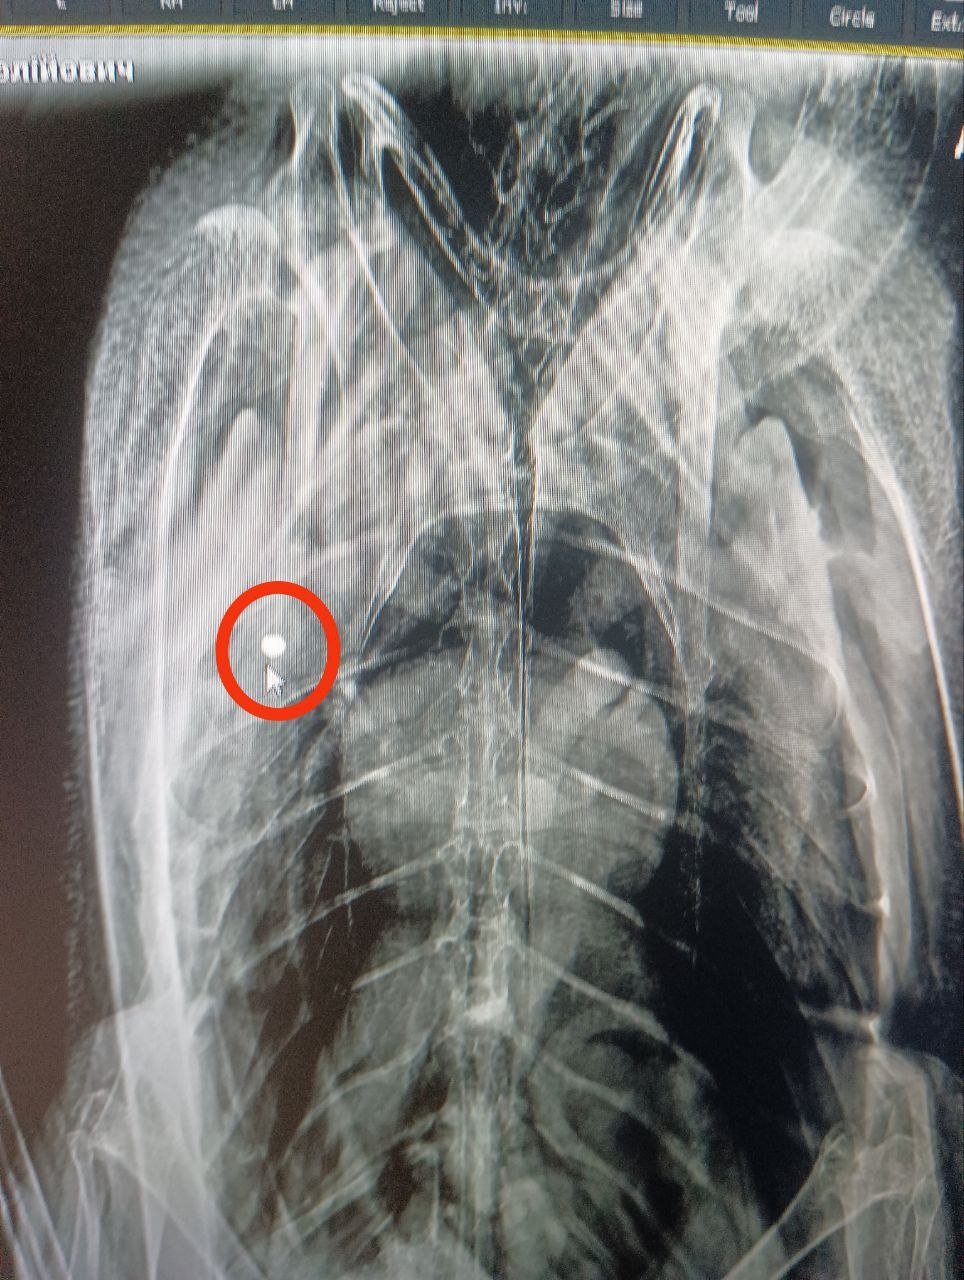

Після цього птахів відвезли до ветклініки на рентген. Волосінь фахівці так і не знайшли, зате знімок показав у тілі одного з лебедів дві кулі від пневматичної зброї.